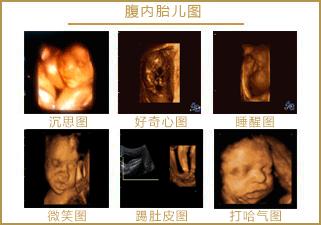

见诸各大网站的3D胎儿图像,也展示了胎儿在19周时微笑的模样,栩栩如生,惹人喜爱。

怀孕5个半月,胎儿已经有了面部表情,喜怒哀乐都会有,当然胎儿也会发笑。

5个半月的胎儿大脑发育趋于完善,能够控制感觉器官,使面部具有丰富的表情。感觉器官迅速分化,味觉、听觉、触觉、视觉、听觉等都在大脑中占据了一定的空间,神经元之间的连接也开始增加了。

5个半月的胎儿相当于22周,眼睛、鼻子、眉毛、耳朵、嘴巴等五官面貌结构完整,嘴巴、眉毛活动自如,面部表情丰富也很正常。

从这里看出,在做四维彩超的时候很容易捕捉到胎儿的微笑,这时不要觉得奇怪,这是胎儿正常的生理反应。